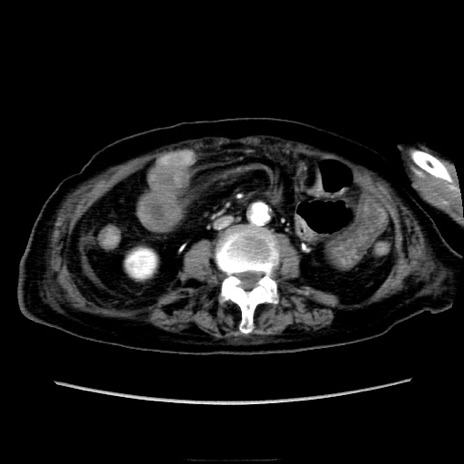

症例40(横断像)

【症例】90歳代女性

【主訴】腹痛・嘔吐

【現病歴】 食欲低下、嘔吐があり昨日他院受診。肺炎と診断され入院となる。入院後より腹部全体に圧痛あり。胃管留置され経過みていたが、症状持続するため、

当院転院となる。

【既往歴】胸椎圧迫骨折、胆石症

【身体所見】腹部:中央に激痛あり、圧痛あり、反跳痛不明

【データ】WBC 17100、CRP 18.82

横断像